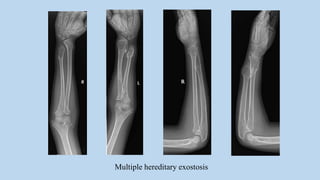

Diaphyseal aclasia (multiple hereditary exostosis)

• A rare autosomal disorder with multiple osteochondromas

• Particularly at the ends of the long bones, ribs, scapulae and iliac bones

• Shortened or deformed limbs

• Metaphyses can be widened and dysplastic

• Vertebral involvement is rare

Multiple hereditary exostosis

Diaphyseal aclasia (multiplehereditary exostosis) • A rare autosomal disorder with multiple osteochondromas • Particularly at the ends of the long bones, ribs, scapulae and iliac bones • Shortened or deformed limbs • Metaphyses can be widened and dysplastic • Vertebral involvement is rare